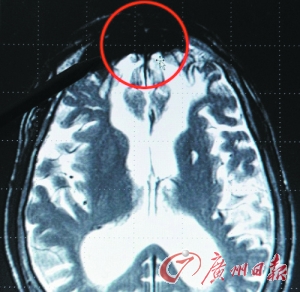

不莱梅大学的杰哈德・罗斯展示从罪犯大脑前下方发现的“罪恶斑”。

扫描图像上,罪犯大脑前下方的黑斑清晰可见。该黑斑被罗斯教授称为“罪恶的渊薮”。

“当你对惯犯的大脑进行扫描的时候,你能看到他们大脑的前下方总是有严重的缺陷。”罗斯告诉《每日邮报》,“由此证明,一个人犯罪,往往是因为他大脑的那块区域出现了肿瘤或者受到了损伤。只要通过外科手术摘除肿瘤,他又完全可以恢复正常……那块地方正是罪恶的渊薮。”单胺氧化酶基因起作用